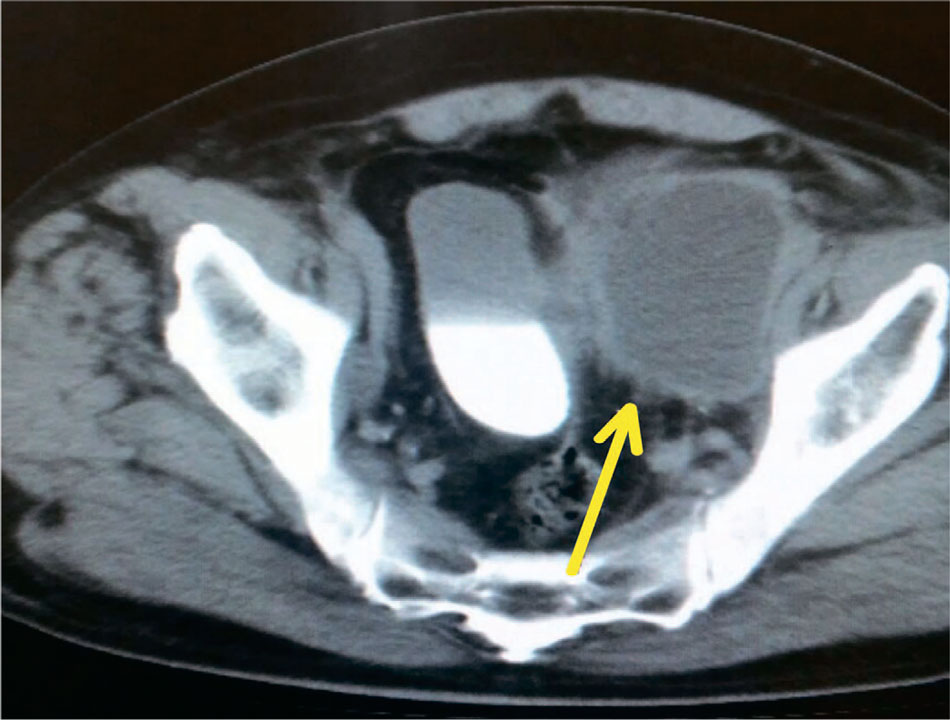

Основные осложнения в позднем послеоперационном периоде у пациентов, перенесших РПЭ с лимфодиссекцией являлись формирование лимфокист с воспалительным компонентом (рис. 7).

Рис. 7. КТ-картина лимфоцеле, сформировавшегося слева, с признаками воспаления

Fig. 7. CT scan of a lymphocele formed on the left side with signs of inflammation

Развитие лимфокист после проведения лимфадэнэктомии в комбинации с радикальной простатэктомией было отмечено у 7 больных и было обусловлено сложностью хирургического вмешательства и неизбежным нарушением целостности лимфатических сосудов, несмотря на высокую точность техники. При этом возникшие внутрибрюшные и ретроперитонеальные ограниченные жидкостные образования подвергались инфекционному заражению. Все образовавшиеся локализации были эффективно дренированы с использованием перкутанной методики под ультразвуковым наведением. В одном случае, при отсутствии эффекта от дренажа и продолжающейся лимфорреи, была проведена фенестрация лимфокисты через брюшную стенку с помощью лапароскопии.